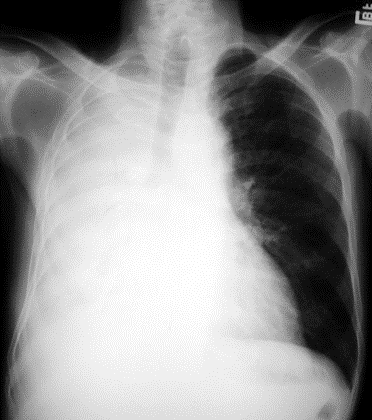

Pacients ar labās puses totālu hidrotoraksu; kāda perkutorā atradne sagaidāma virs labās plaušas?

0%

100%